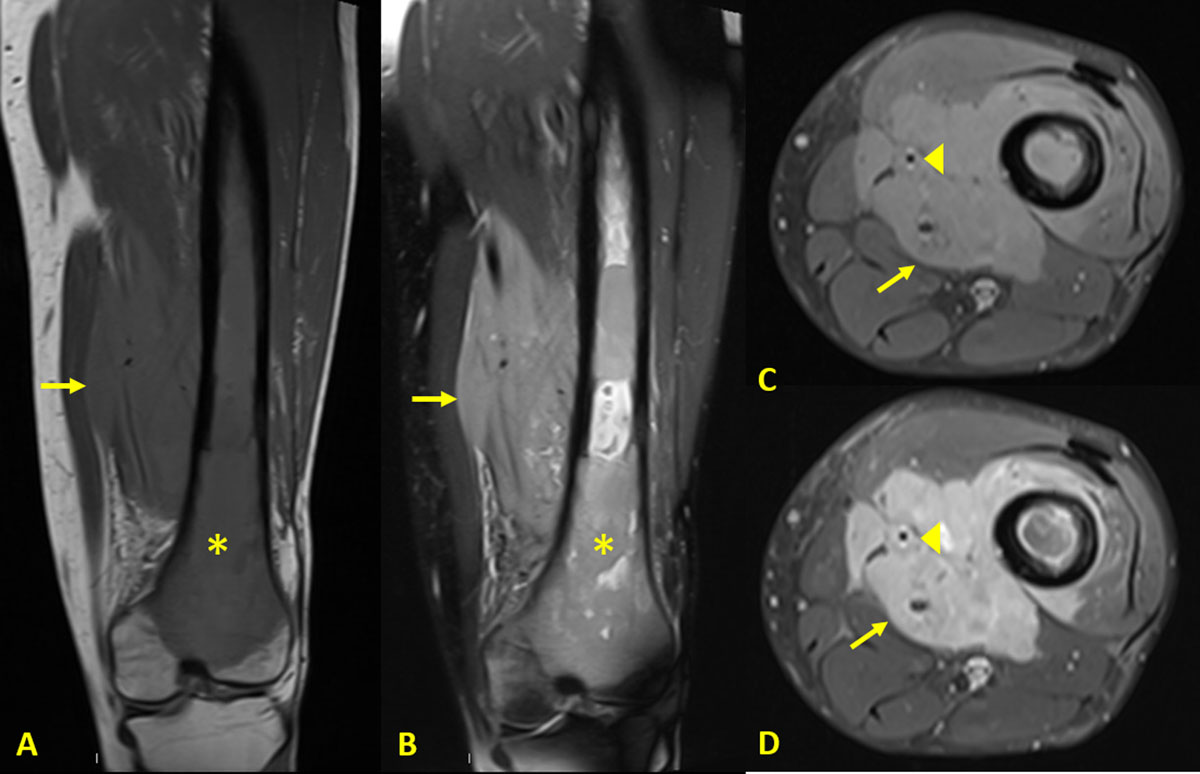

Figure 3

MRI of the knee showing a large soft tissue mass infiltrating the thigh’s muscles.